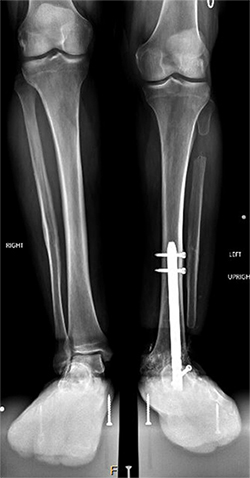

The operation took place in November 2022. Because Natale’s ankle was fused, Marecek chose to lengthen Natale’s tibia, or shin bone, rather than his femur. Marecek also identified that Natale’s ankle had been fused out of alignment. So, first he corrected the ankle’s alignment, then he broke Natale’s tibia and inserted a distraction rod—the kind that could push the two sides of the broken bone apart.

Natale could not put any weight on the leg for three months. After that the distraction rod was removed and replaced by a weight-bearing rod.

Natale says he had to do a lot of physical therapy, stretching the muscles to make space for the longer leg bone. It was about six months before Marecek gave him the go-ahead to put his full weight on it. Even after a year, X-rays showed the bone still hadn’t completely filled in the gap around the rod in his tibia.